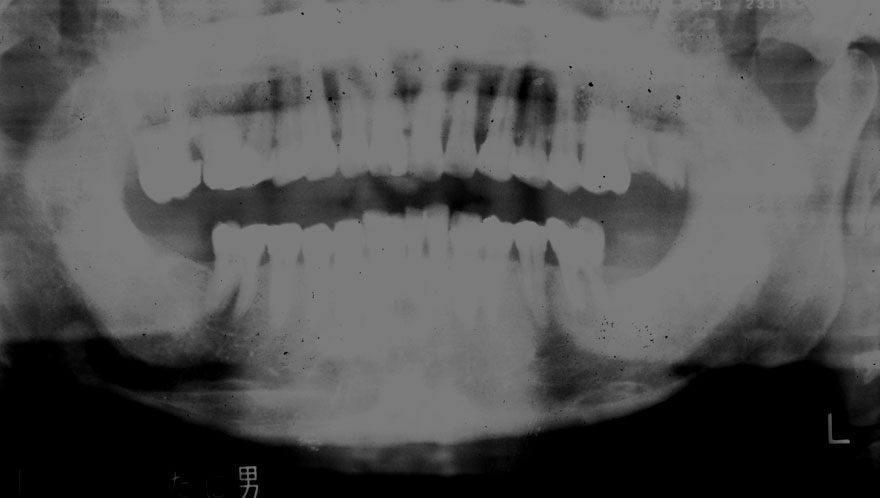

初診時 50歳 女性

河田歯科医院

30年後 80歳